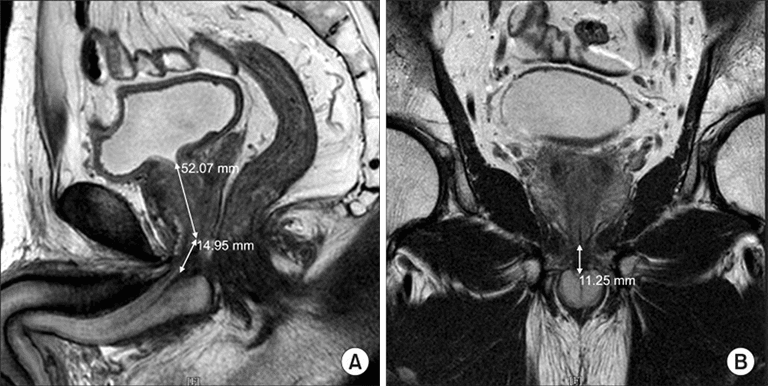

Gemeinsam mit dem Prof. Stehling Institut für Bildgebende Diagnostik haben wir spezielle bildgebende Verfahren entwickelt, um die kritischen anatomischen Strukturen am Beckenboden sichtbar zu machen, darunter die dynamische Darstellung des Beckenbodens unter Belastung und die hochauflösende Darstellung des Harnröhrenschließmuskels.

Dadurch können wir die Behandlung mit Stammzellprodukten genau auf den Bereich ausrichten, in dem die Stammzellen am meisten benötigt werden. Mit dem Stammzellsekretom können wir den Harnschließmuskel perfundieren, um seine Funktion zu reaktivieren, ohne die empfindliche anatomische Struktur des Schließmuskels zu beschädigen. Dies ist einer der vielen Vorteile gegenüber chirurgischen Eingriffen, die unweigerlich zu einer teilweisen oder vollständigen Zerstörung des Schließmuskels führen.